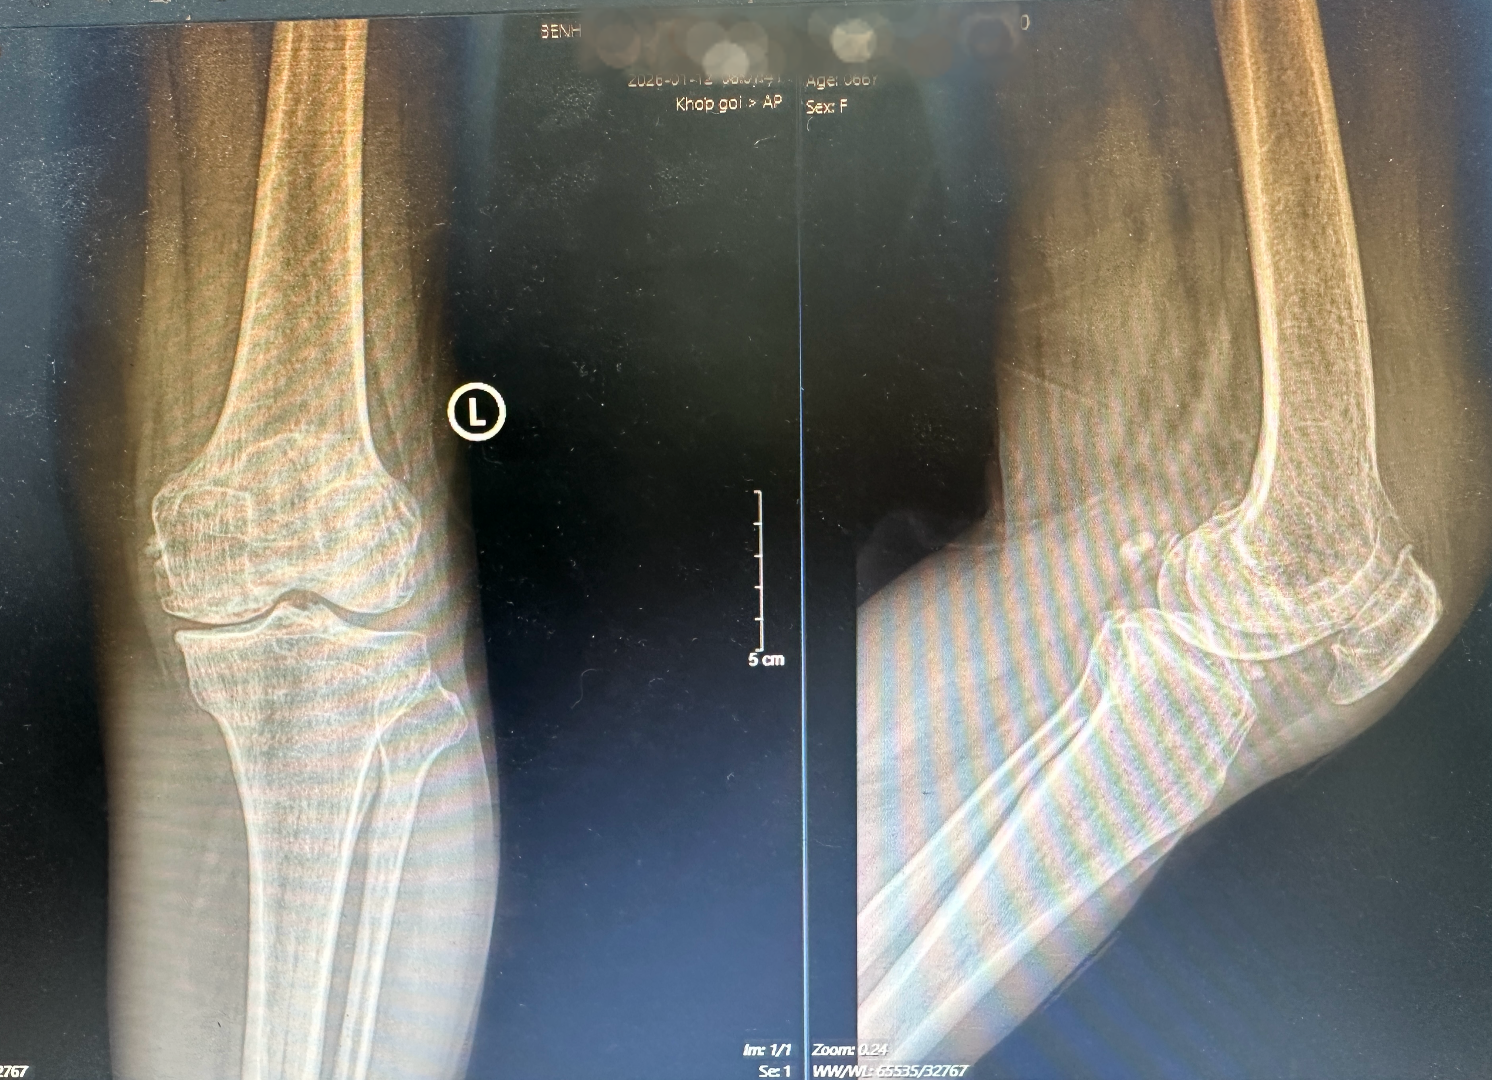

Hình ảnh phim chụp X – quang khớp gối trước mổ bị thoái hóa giai đoạn 3 – 4, nhiều gai xương, khe khớp hẹp và chân lệch trục

Thời điểm thăm khám tại Bệnh viện Hữu nghị Việt Đức, tình trạng khớp gối của người bệnh ảnh hưởng đáng kể đến chức năng vận động, đau nhiều, dáng đi lệch trục, hai chân “cao – thấp” rõ rệt do khớp tổn thương kéo dài.